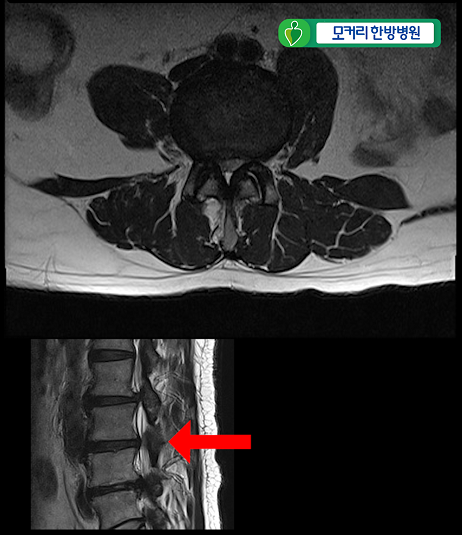

<3-4번>

이 환자분은 협착증을 25년간 앓으시고 증상도 매우 심하신 환자분입니다.

허리 세 마디 2번 3번, 3번 4번, 4번 5번, 이렇게 세 마디의 척추관이 심하게 막혀 있습니다.